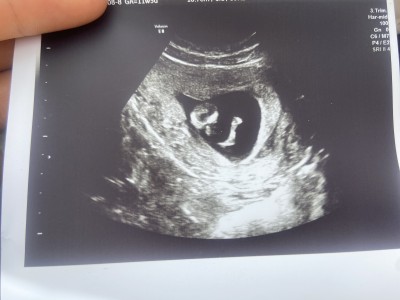

Resimli bakın size zahmet 🙏

Gebelik haftası 11+5

Yüzde yüz kız 😁🥰

Kesinlikle nub yani genital çıkıntı 30 dereceden küçük ve net belli kesinlikle yüzde yüz kız

Kız çocuk bence sağlıkla gelsin canım nub u yukarda değil

Kız canım aynı hafta aynı fotoğraf bendr de var şuan 20 haftalık ve kız 3 farklı doktor bana kız dedi doktordan önce kendim de görmüştüm aynısı sendr de var hayırlı olsun